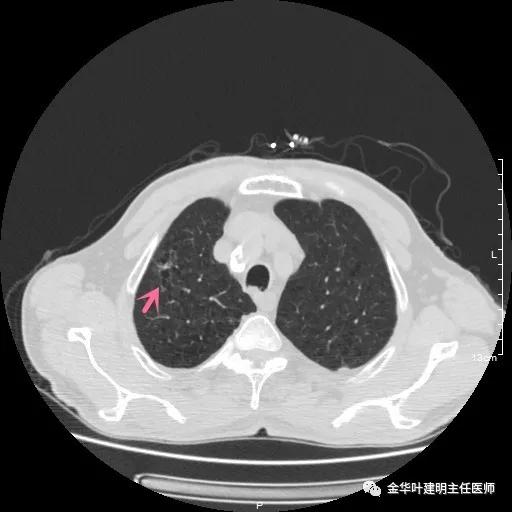

以上示右下叶病灶5。也是主病灶,是实性块状分叶的占位性病变,基本可以肯定是肺癌。单病灶看需下叶切除并清扫淋巴结。